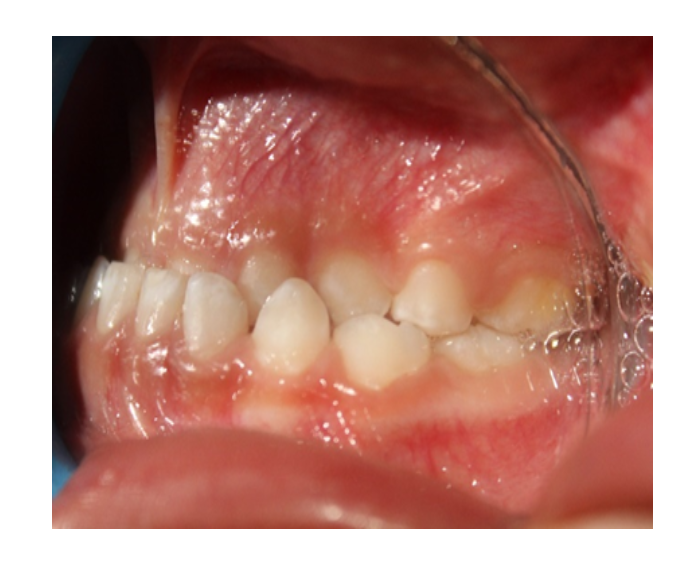

Mordida Cruzada posterior unilateral